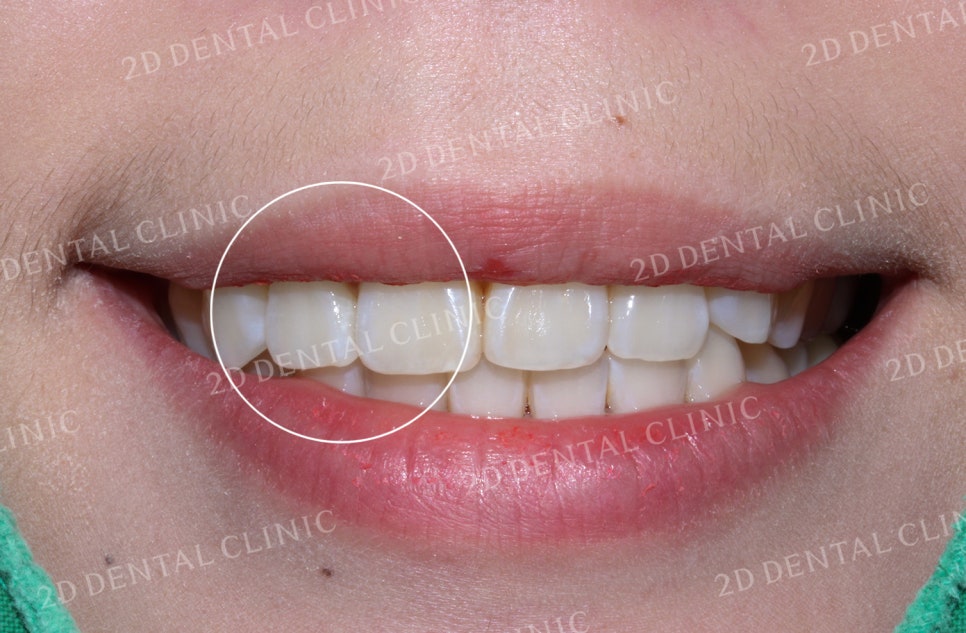

교정 전 환자분의 전치부 사진입니다.

전체적인 교합 상태가 나쁘지 않고

어금니 부근도 부정교합 없이

바르게 물리고 있습니다.

다만, 치아의 정중선이 맞지않아

상악과 하악의 위치가 틀어져

있는 것이 확인됩니다.